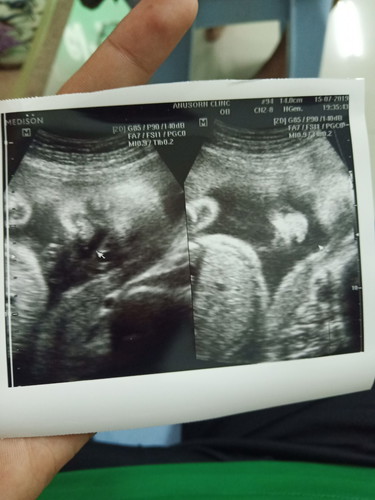

กำหนดคลอด 12 ตุลา อัลตราซาวนด์วันนี้น้องน้ำหนัก 1,070กรัม ถือว่าปกตินะคะ น่าจะตัวใหญ่ด้วย 6 เดือน หนักขนาดนี้55555

บ้านนี่ กำหนดคลอด27ตุลา ลูกหนัก700กรัมค่ะ